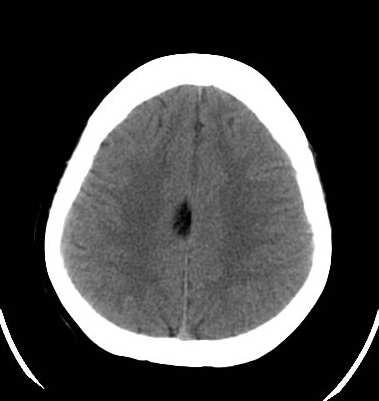

脑外伤患者,无外伤性改变

胼胝体脂肪瘤

平均ct值 -60hu

胼胝体脂肪瘤。

小乔(楼主)说:平均ct值—60hu。考虑脂肪瘤。

ct值-60应考虑:脂肪瘤.

颅内脂肪瘤系因隶属于中胚层的脂肪掺合进正在关闭的神经管之中,绝大多数见于胼胝体膝部,肿瘤较小;偶尔可发生在整个胼胝体,肿瘤较大。颅内脂肪瘤也可见于四叠体池,鞍上池,大脑脚池以及桥小脑角池。约有50%的中线脂肪瘤并有胼胝体发育不全,但是,胼胝体发育不全很少并有脂肪瘤。胼胝体脂肪瘤有症状的仅占一半,主要为癫痫,痴呆,头痛,半身不遂。癫痫系因脂肪瘤使邻近的纤维性结缔组织浸润到周围脑组织所致。脂肪瘤占位效应不明显,由于它浸润性生长,有时可造成对邻近血管如大脑前动脉的包绕,可影响正常脑脊液通路而导致脑积水。

颅内脂肪瘤少见,占颅内肿瘤的1%以下。有人认为不是肿瘤,而是原始脑膜组织的畸形。好发于胼胝体及其周围。胼胝体区脂肪瘤多并发于胼胝体发育不良。瘤体呈圆形或分叶状,大小不等,境界清楚。ct上,病灶呈脂肪密度的圆形或分叶状肿块,周边可见弧形钙斑。无瘤周水肿。无强化。本例发生于胼胝体区低密度肿块,ct值-60,应是典型的胼胝体区脂肪瘤。